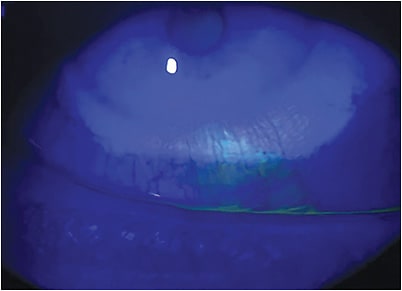

Unwanted Retention of Contact Lenses in the Eye While there have been no large-scale studies of either long- or short-term ocular lens retention, the publication of case reports is common—especially those describing long-term lens retention. Typically, these cases are reported because of the unusually long periods during which the lens has remained undetected in the eye, or some other distinguishing feature considered worthy of discussion (e.g., a recent report linked to unusual orbital anatomy, another relating to the development of conjunctivitis, and in extreme cases the need for surgical intervention to remove a lid cyst or tumor that has developed in response to lens retention).14-25

Of course, most cases may be prevented by regular review, which involves lid eversion and possibly double lid eversion.4 Yet, without any clinical indication to do so, how often would an ECP routinely evert a patient’s eyelids during a sight test? Would someone reporting a vague history of past lens wear provide sufficient impetus to warrant lid eversion? We suspect not, but perhaps the regular trickle of case studies reporting long-term lens retention should encourage practitioners to reconsider how we approach patient lens handling training.